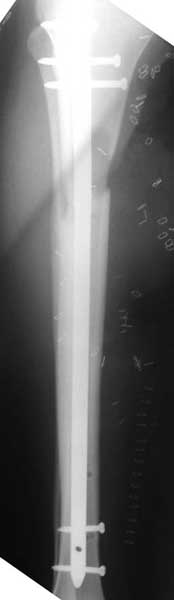

Flaped within week. Frame removed and converted to nails (retro femur) prior to flap. Had proximal tibial defect after initial debridement. Soft tissue envelope healed.

S/P Nailing

AP

lateral

ST healed